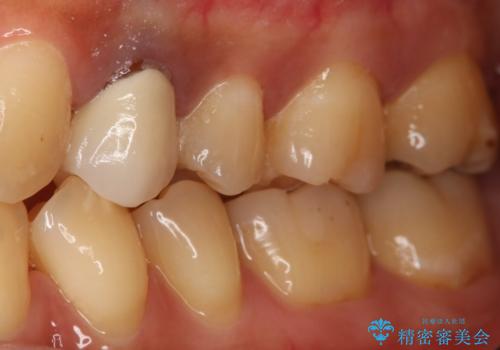

う蝕除去中に露髄 フルジルコニアクラウン

- 左上5番のう蝕治療を希望された患者様です。

う蝕が神経近接にまで達していたので露髄する可能性を説明しました。

その場合、精密根管治療・クラウンになることもお伝えしています。

う蝕除去中に露髄したため精密根管治療へと切り替え、仮歯をはさんでセラミッククラウンを装着し終了としました。